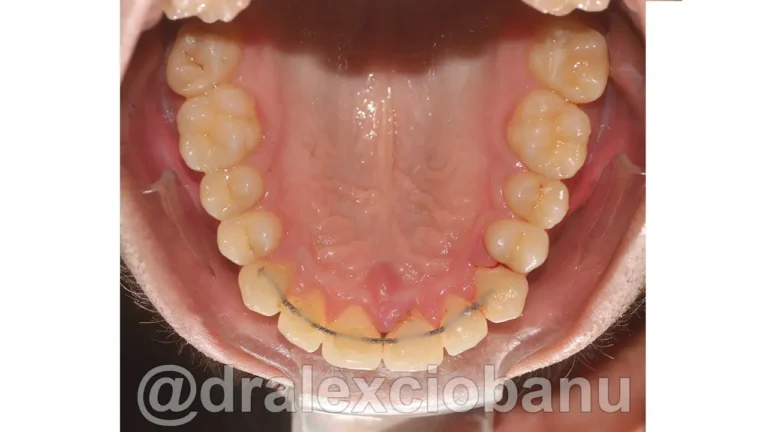

Il paziente presentava una malocclusione di prima classe per grave affollamento dentario superiore ed inferiore.

Al fine di garantire un alto livello di estetica e precisione maggiore nello spostamento dei denti, sono stati applicati degli attacchi linguali 3D WIN LINGUAL SYSTEM in entrambe le arrecate.

I brackets linguali possono allineare sia le corone che le radici dei denti, in modo che siano perfettamente posizionati l’uno accanto all’altro in posizione corretta. È spesso difficile ottenere questo posizionamento utilizzando gli allineatori rimovibili, specialmente quando si tratta di correggere le rotazioni dei canini. I brackets linguali fissi possono posizionare perfettamente i canini e i denti anteriori nella posizione corretta, come mostrato nella radiografia orto panoramica al termine della terapia.